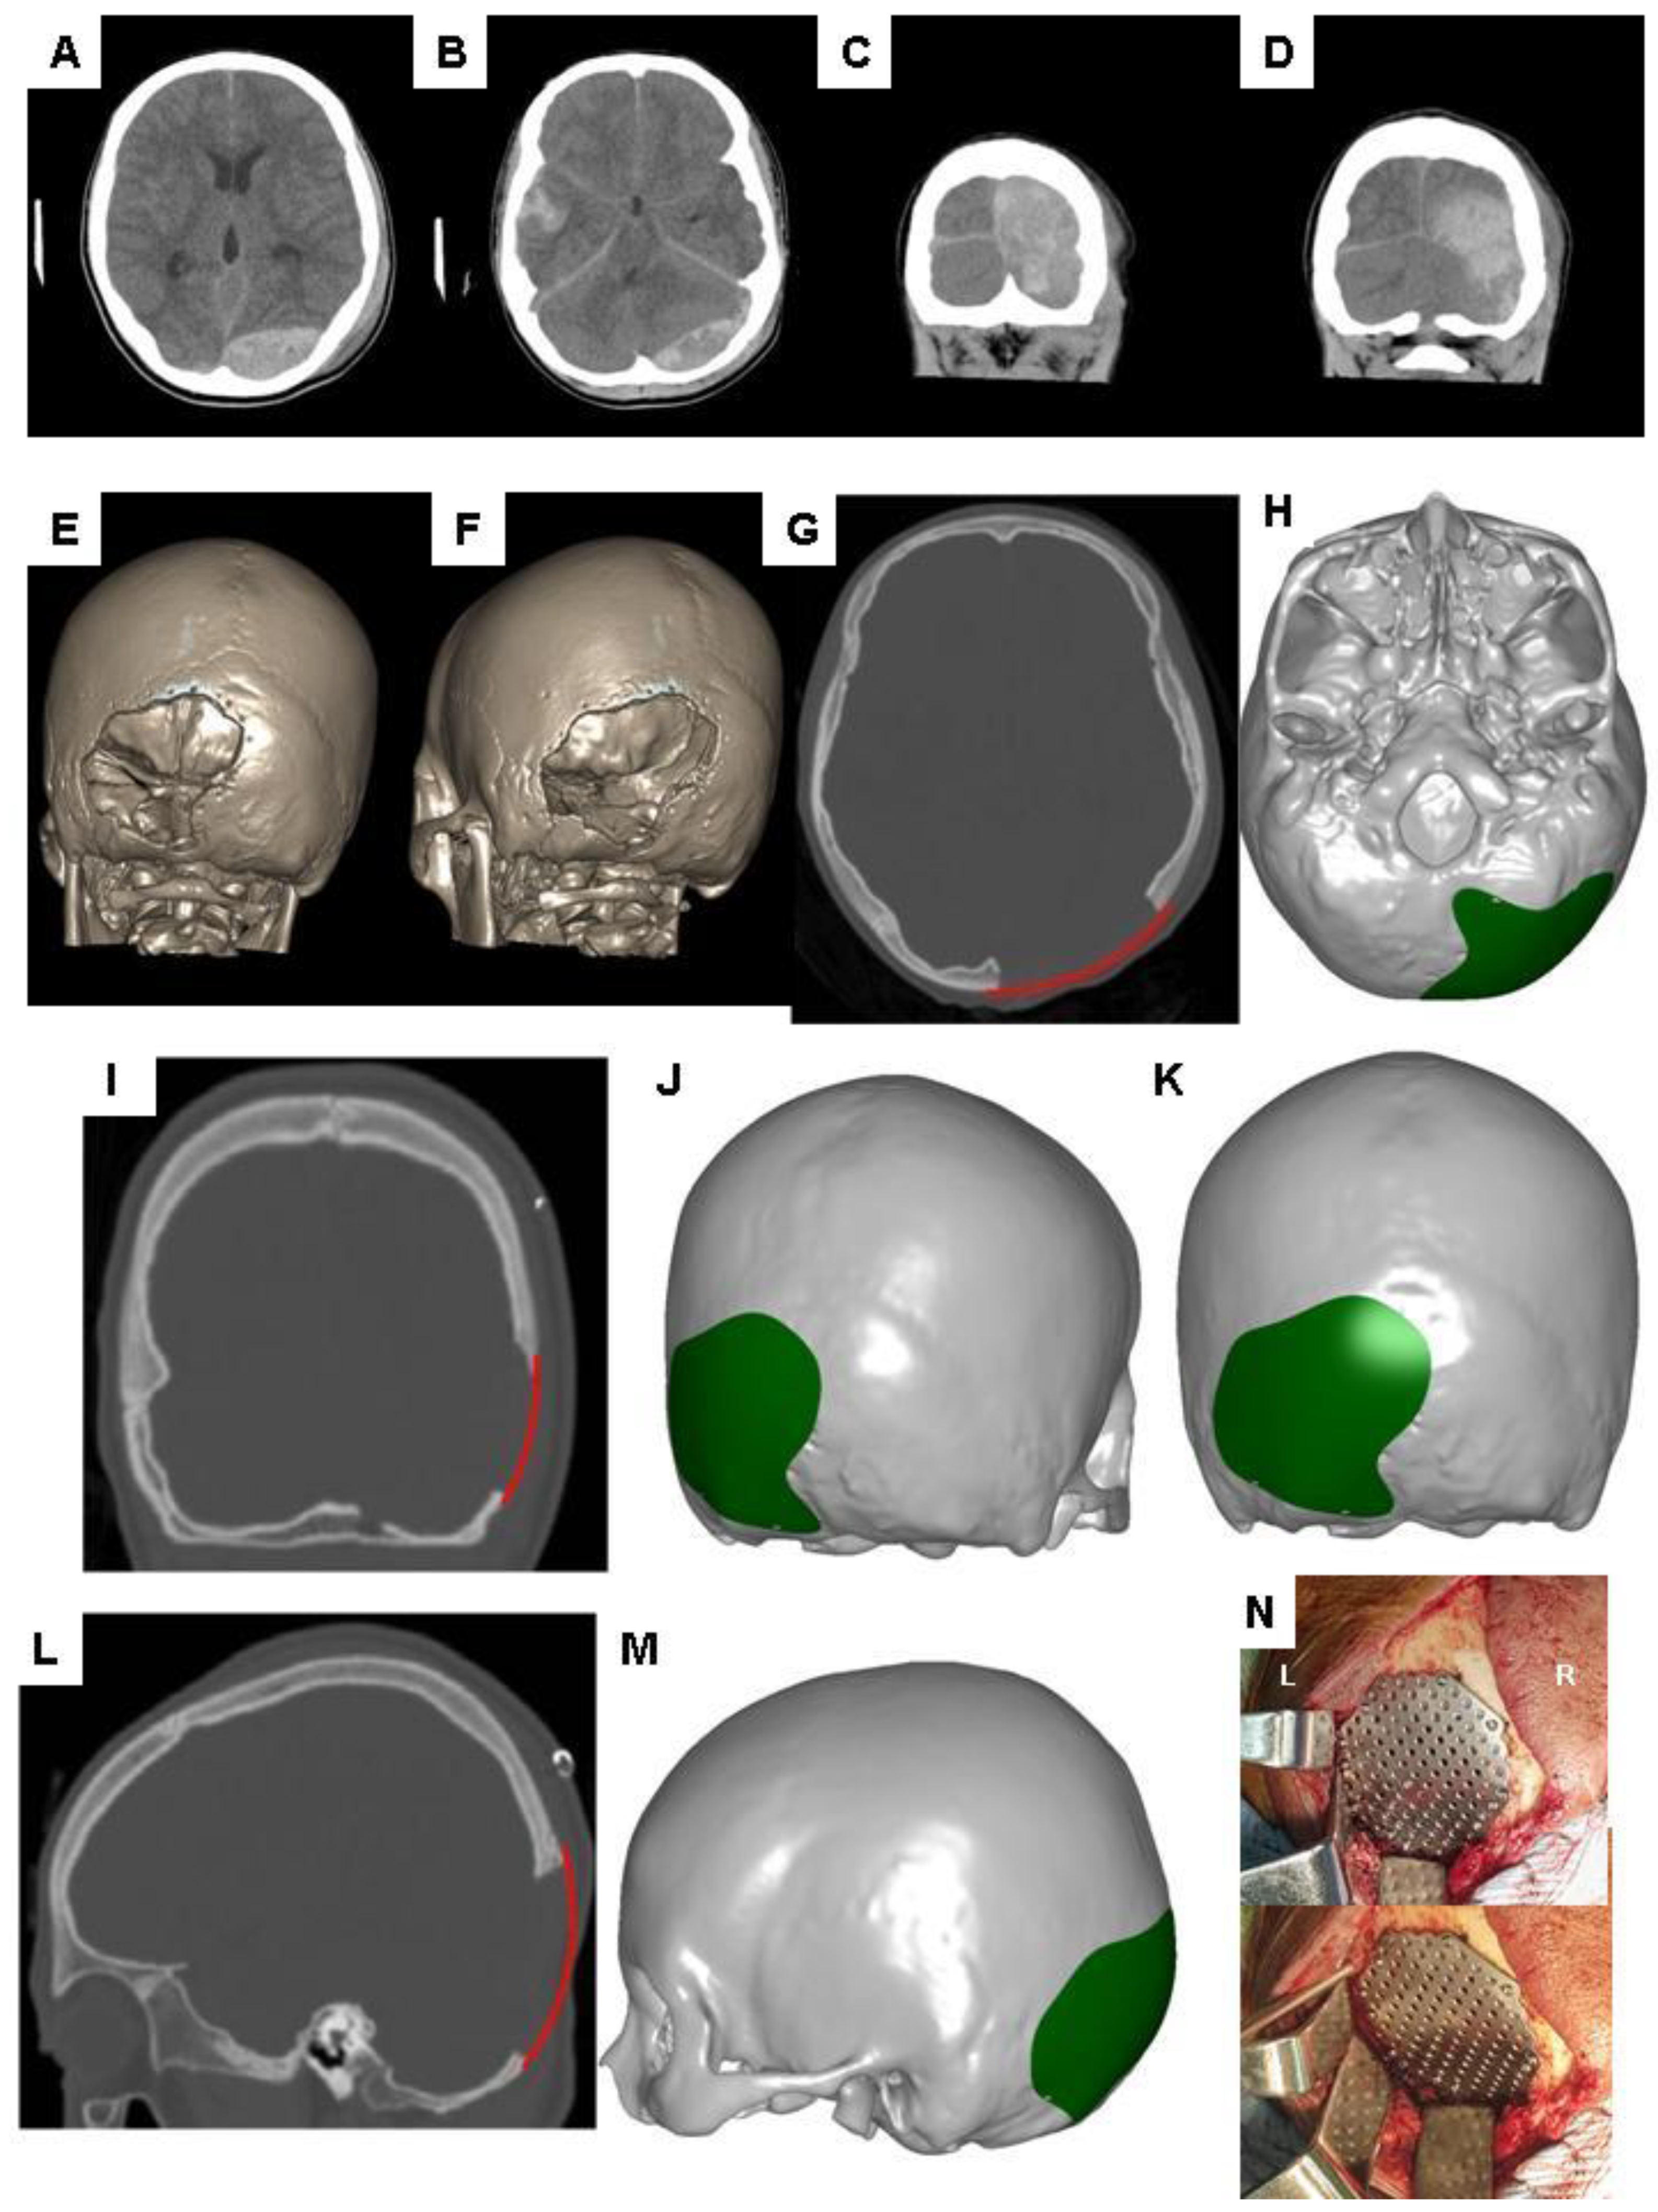

6. Brief Overview of the CAD Modeling Process for the Reconstruction of Cranial Defects

7. Demonstration of Editing the 2-D Images of Brain CT Scans Using Commercial Software

8. Brief Overview of CAM Processing for Reconstruction of Cranial Defects

9. Clinical Consideration of CAD Algorithms for Adjusting Contours

10. Demonstration of Adjusting Contours for the Reconstruction of Skull Defects in CAD Modeling